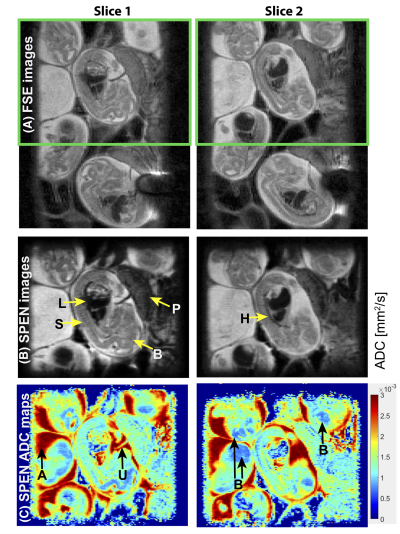

5. A new approach for multislice spatiotemporal encoding MRI in a portable low‐field system.png

Qiu Y, Chen S, Solomon E, Wang C, Zhong S, Dai K, Chen H, Frydman L, Zhang Z

Magnetic Resonance in Medicine, 2024